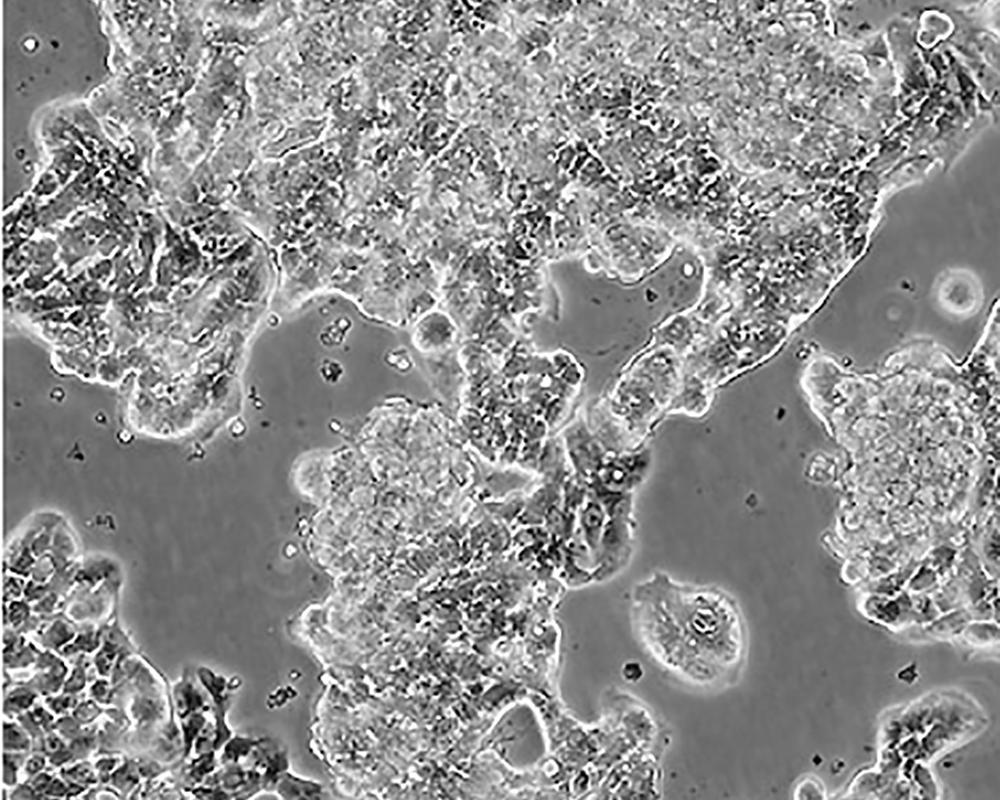

ZR-75-1 [ZR751]

中文名稱 人乳腺癌細胞

組織來源 浸潤性導管癌;腹水轉移;女性

生長特性 adherent

形態特征 epithelial

細胞描述 該細胞產生高水平的黏液素MUC-1 mRNA,低水平的MUC-2 mRNA,但不表達MUC-3基因;表達雌激素受體。